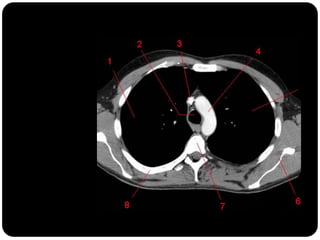

 TC janela de mediastino com contraste

TC com janela para mediastino com contraste